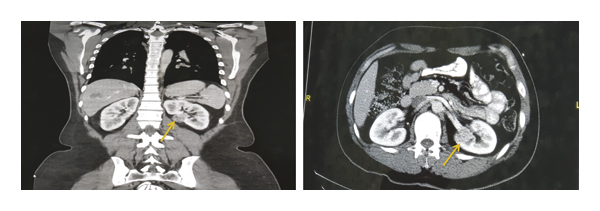

CT abdomen was performed and showed well-defined hypodense focal lesion originally from the left kidney near hilum region with clue sign. The renal lesion shows inhomogeneous enhancement in the arterial phase with partial wash out in delayed phase, it measured 2,6 cm × 2,6 cm, to rule out the possibility of renal cell carcinoma as shown in Figure 1.